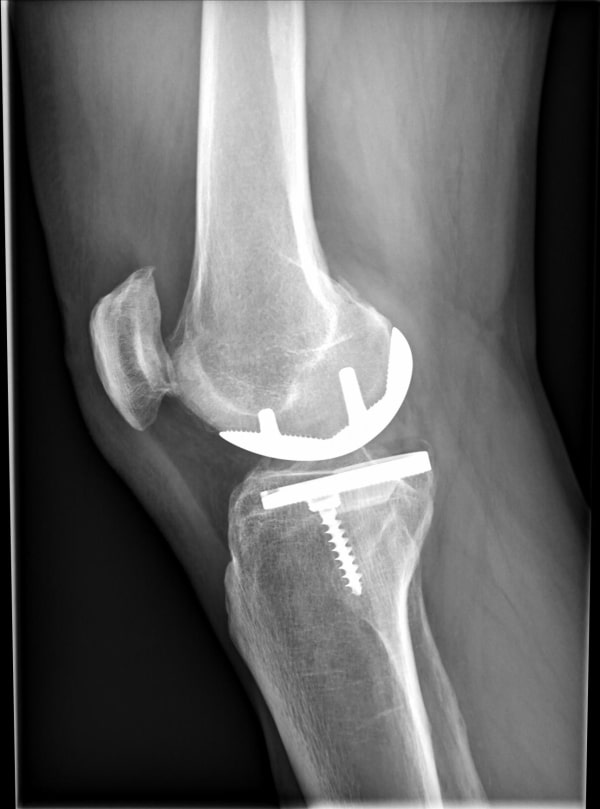

Si on me pose une prothèse unicompartmentale, n’y a‑t-il pas un risque de devoir réintervenir plus tard pour une prothèse totale du genou ?

Non, ce n’est pas une évidence. Un remplacement par une prothèse totale de genou dépendra de l’apparition ou non de signes cliniques et radiologiques d’arthrose sur les autres compartiments du genou à long terme. En cas d’usure isolée du polyéthylène (pièce en plastique entre les 2 surfaces métalliques qui remplacent le cartilage usé), il est possible de changer uniquement cette pièce. Mais cela reste rare, j’ai le souvenir d’avoir repris un cas pour ça depuis que j’implante des prothèses de genou en Ille et Vilaine.

C’est seulement en cas de descellement des pièces métalliques que j’envisage un changement par une prothèse totale de genou.